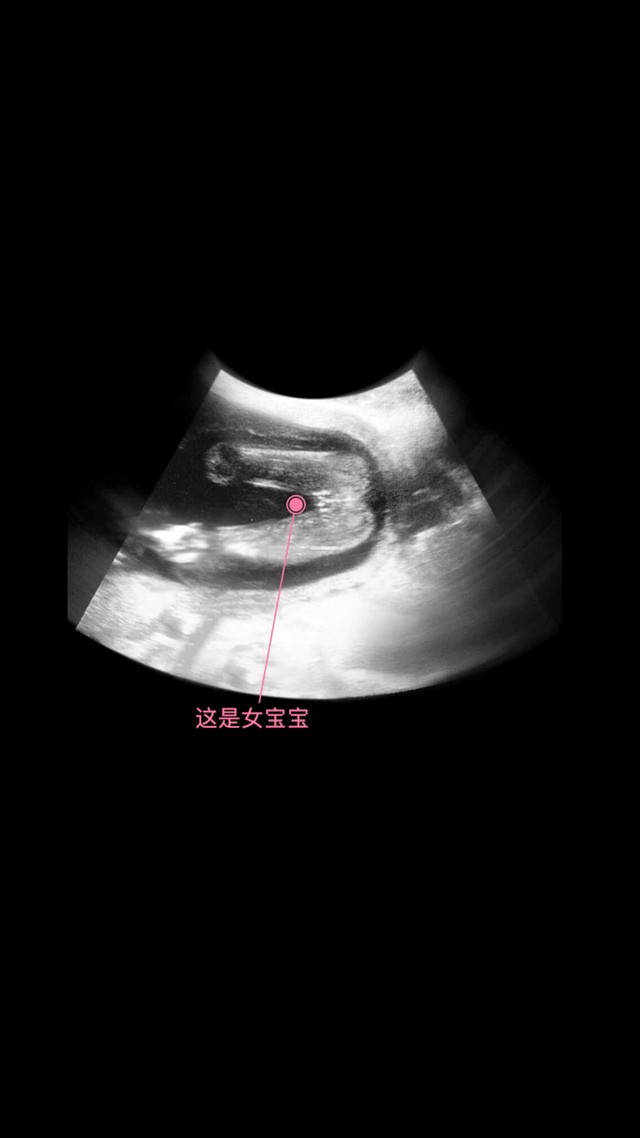

👑Jdan[帖主]:这两个图就是我在美柚上看过的呀,然后才会自己在做四维的时候看出来性别,没说这图是我的娃的

这个是美柚软件里有每周彩超的样子 !15-16周大概能看出来的

👑Jdan[帖主]:我就是在美柚上看到的这两个图,这两图是从美柚那拿过来讲解用的啊